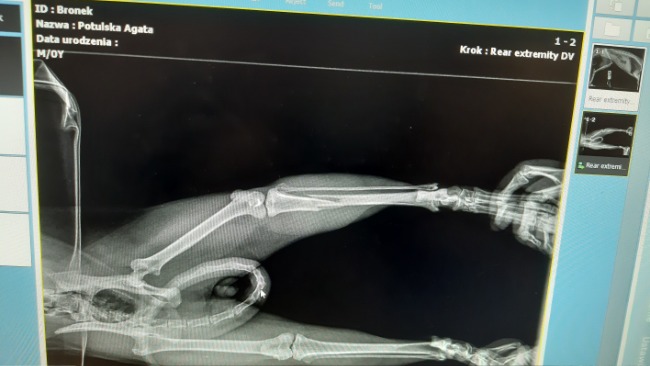

Poniedziałek, dzwoni teflon z prośbą o pomoc dla kota po wypadku. Z informacji uzyskanych od zgłaszającego wynikało, że kota potrącił samochód , który odjechał zostawiając Go na pastwę losu. Nie zastanawiając się ani sekundy , bez planu za co zapłacę w lecznicy, za co utrzymam kota, jadę po biedę !Ona może liczyć tylko na mnie 😔. W lecznicy RTG wykazało złamanie kości piszczelowej.

Bronek tak dostał na imię ddostał leki, dzień później przeszedł operację składania kości.